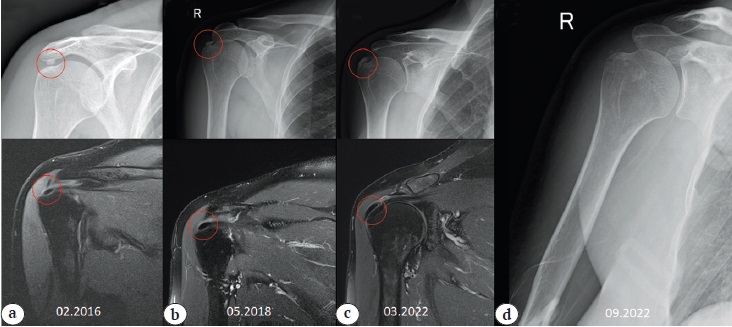

Fig. 1. Case 1. Dynamics of the increase in calcification of the rotator cuff according to X-ray and MRI in the PD mode: a — initial visit: calcification of the supraspinatus tendon; b — increase in calcification after 6 years; c — shoulder joint after removal of the calcium deposit and refixation of the rotator cuff.

Red circle — location of the calcification